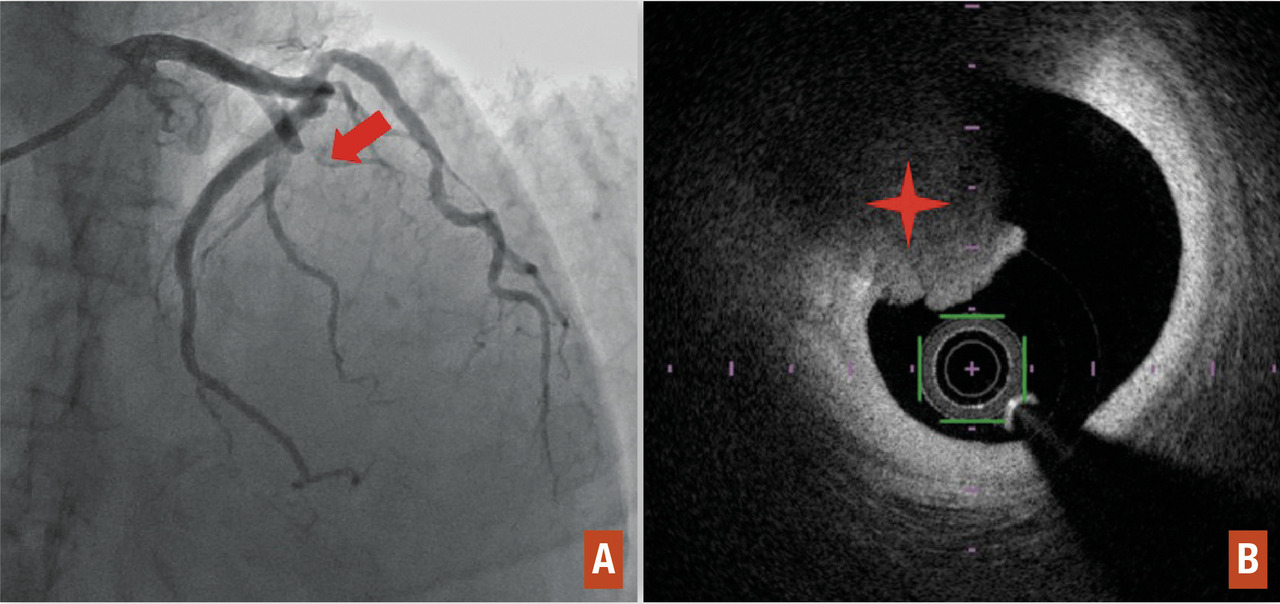

L’IDM de type 1 correspond à une complication aiguë de l’athéro­sclérose dont le mécanisme principal est la thrombose coronaire à l’occasion d’une rupture ou d’une érosion de plaque (fig. 1).

En l’absence de sténose coronaire à la coronarographie, la myocardite, le Tako-Tsubo, un spasme épicardique ou micro- vasculaire, une dissection coronaire spontanée ou un embole coronaire sont des diagnostics à évoquer. Le recours à l’IRM cardiaque, aux tests de provocation (Methergin) ou à l’imagerie endocoronaire est à discuter.